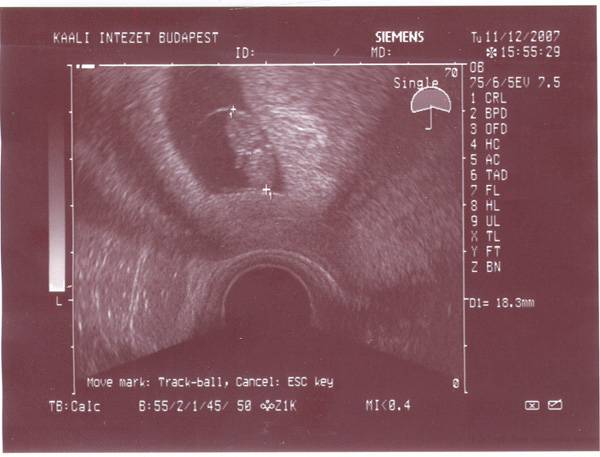

A pici rengeteget mozog, karacsony utan kell mennem egy csomo vizsgalatra ami a szüleshez kell majd, aztan januar elejen megyünk majd az orvoshoz, akkor töltöm a 37. hetet.

Kicsit aggodom, hogy megfordult -e mar, sajnos fogalmam sincs rola de remenykedem...

ez pedig Davide legujabb ajandeka: